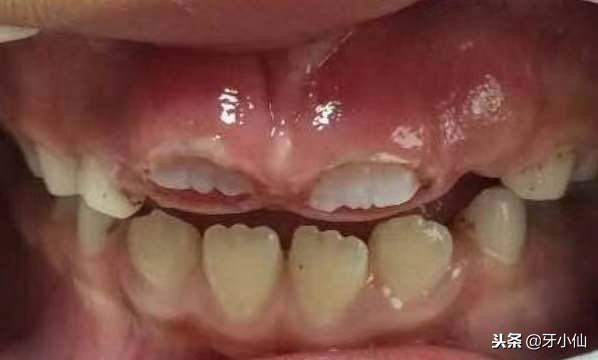

见证奇迹的时刻:

图1

图1: 激光助萌术后,创口小,没有出血图

图2

图2:术后第二天,恒牙萌出

图3

图3:术后第七天,恒牙白白哒